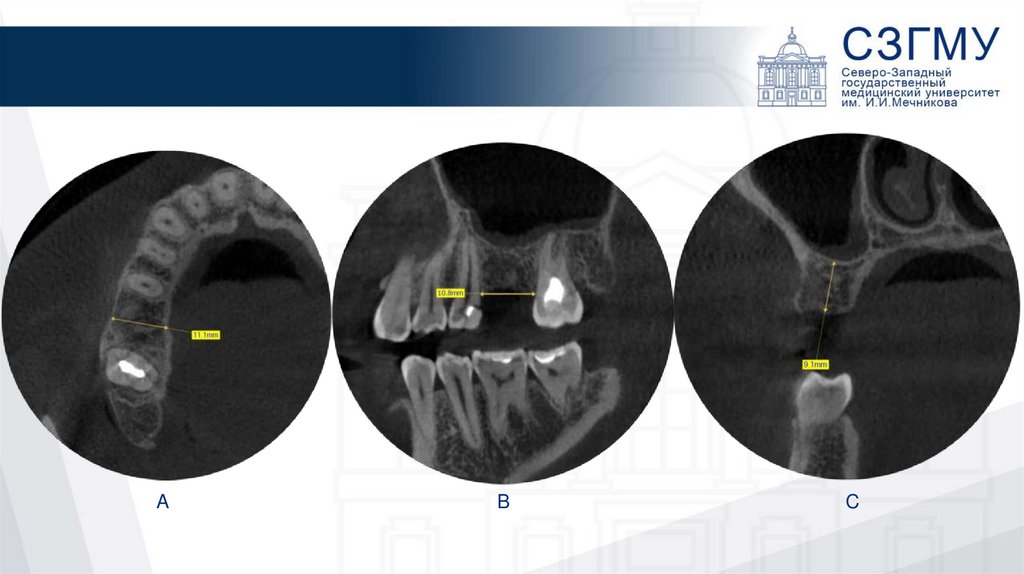

Patient «A» (28 y.o.)

A

B

C